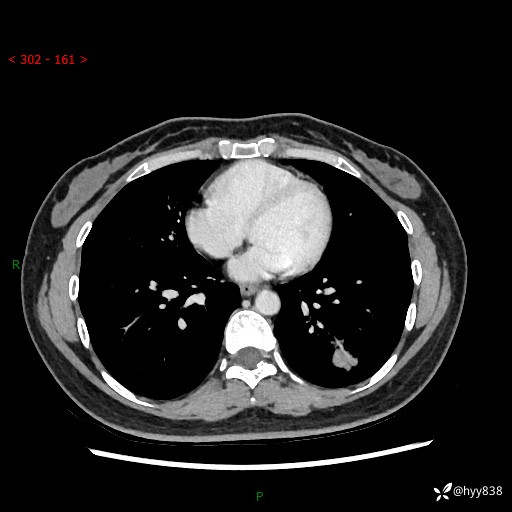

【患者信息】:36岁/女

【主诉】:左侧下胸部阵发性疼痛2周,乏力1周

【现病史及既往史】:患者自诉2周前饮酒后出现左侧下胸部阵发性疼痛,不随呼吸改变,无咳嗽咳痰、头晕头痛、咳血、呼吸困难等不适,于当地第一人民医院查胸部CT提示肺部感染,随后前往我院门诊给予抗感染(左氧氟沙星)治疗1周,自诉胸痛较前好转,感乏力、头晕,偶尔干咳,无咳痰,无发热、畏寒、胸闷、咯血、四肢酸痛、腹泻、腹痛等不适,门诊复查胸部CT提示:左肺下叶感染,病灶较前增加增大,遂以“肺部感染”收入我科。 起病以来,患者精神、饮食、睡眠可,大小便正常,体力体重无明显变化。

【检查】:胸部CT增强(外院平扫)